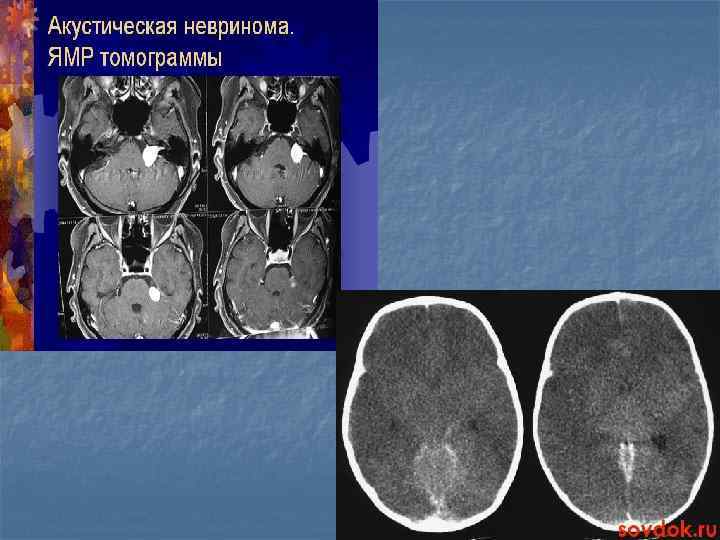

Показания n n n Опухоли различной локализации Эпилепсия(определения очага) Травмы головного мозга Сосудистые нарушения головного мозга Деменции